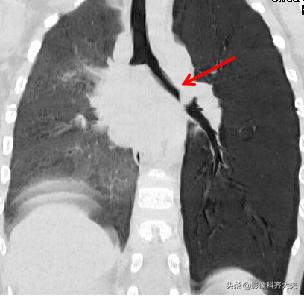

CT冠状位重建明确显示左侧自气管阻塞,有明确异物的存在,红色箭头所示。

图为正位普通X线片,显示左侧明显肺气肿改变,提示左侧支气管异物可能,因家属否认异物吸入,遂进一步做CT确诊。